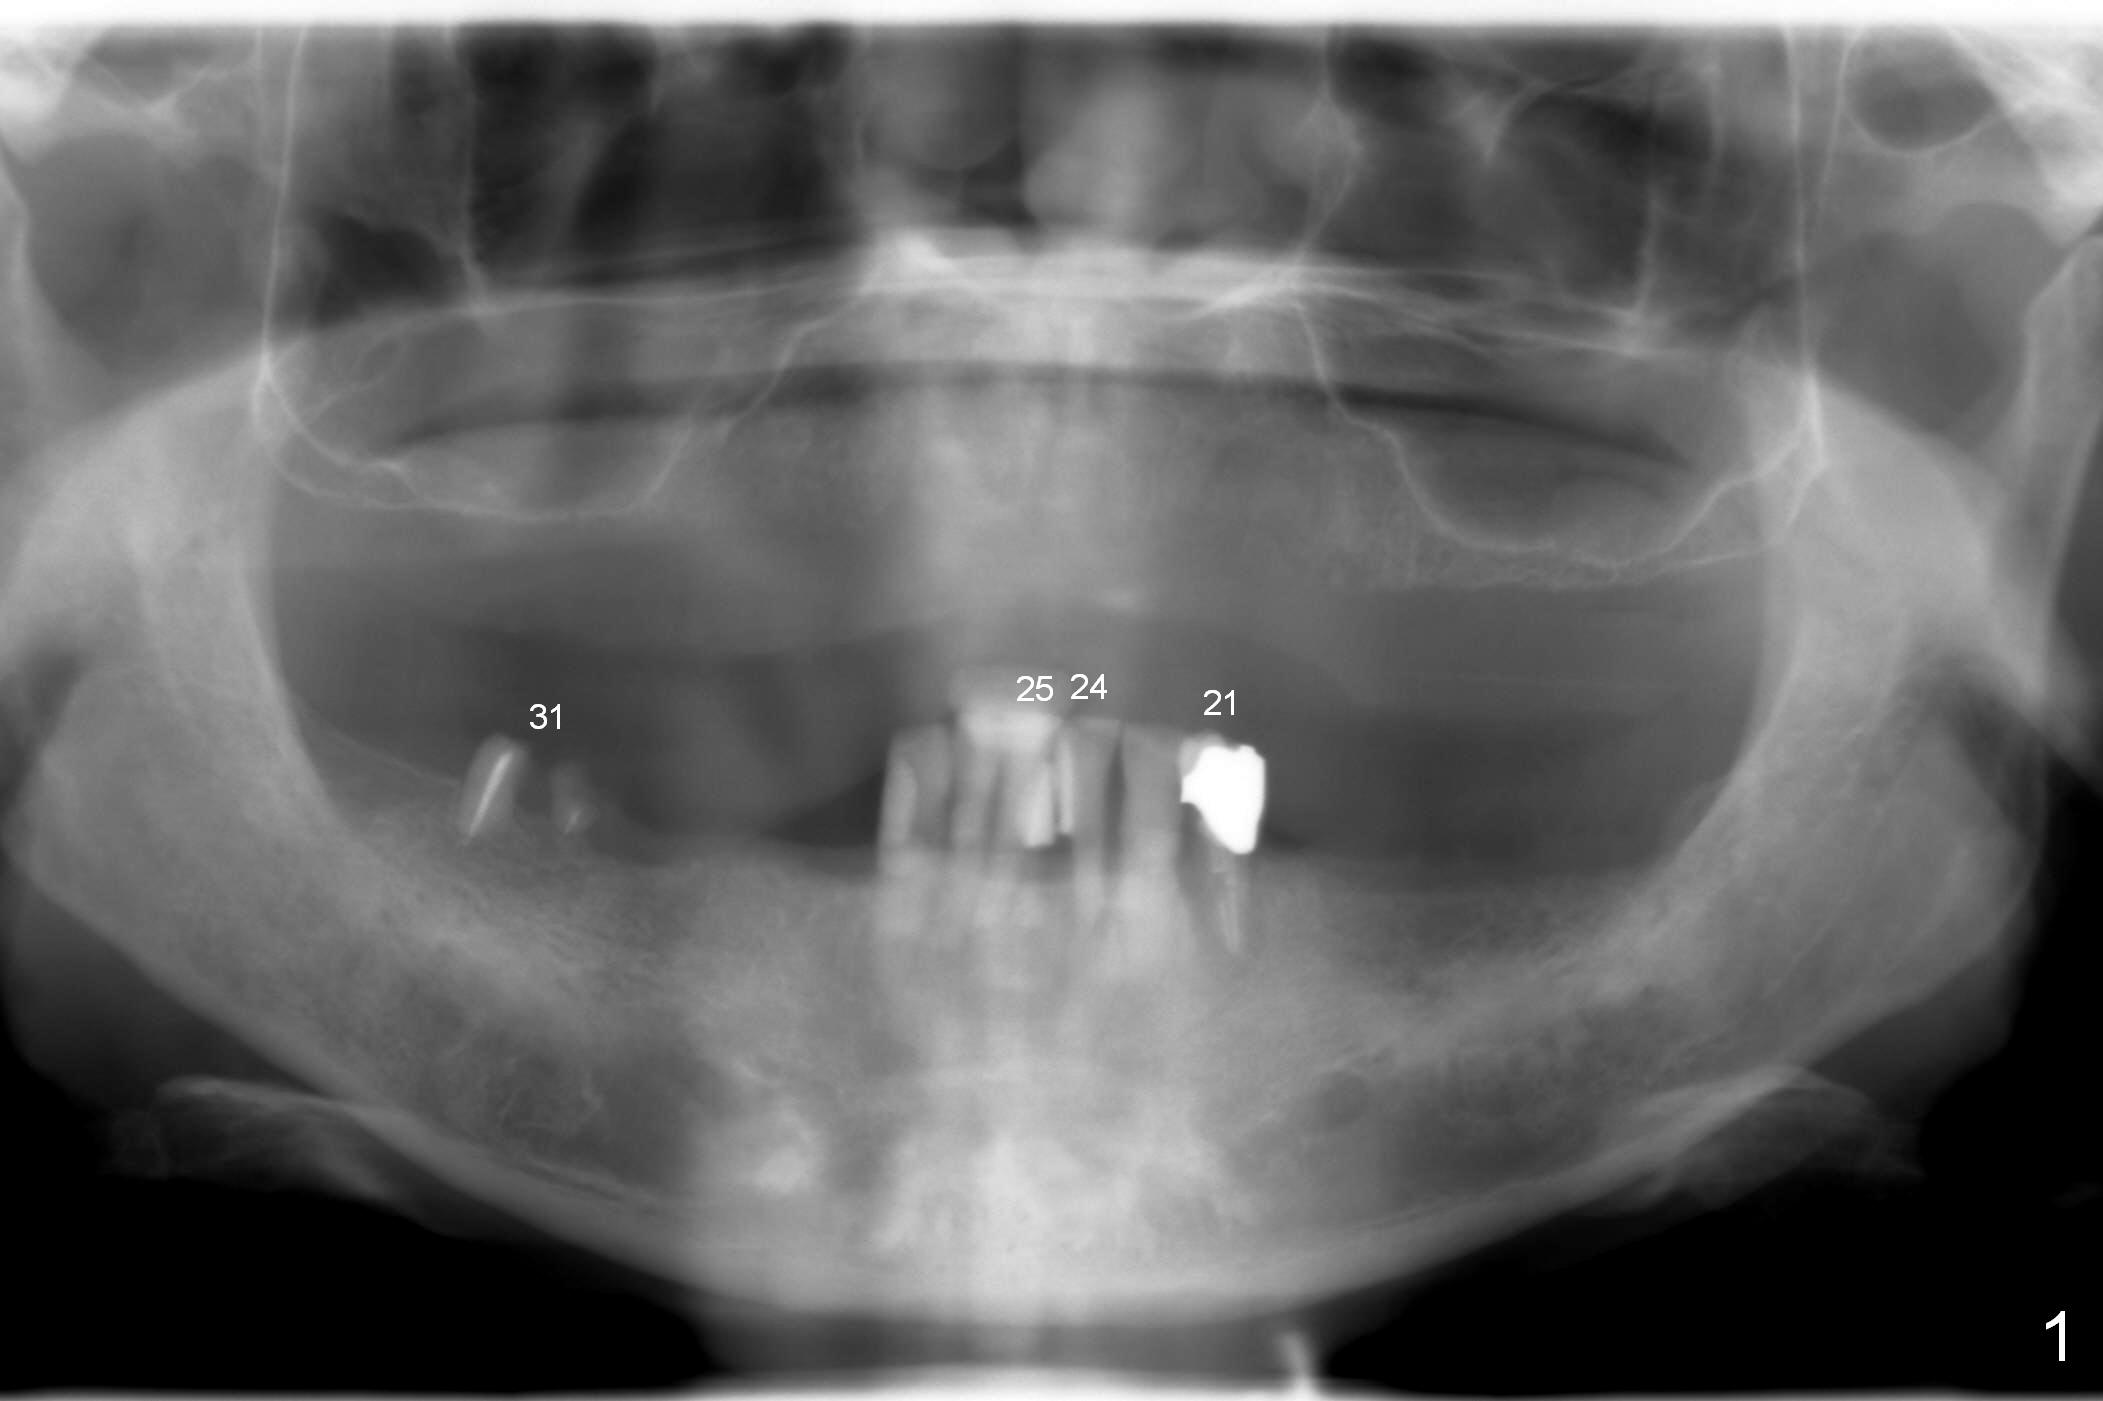

A 72-year-old man presents to clinic for implants because of pain associated with wearing the lower partial. The teeth #21, 24, 25 and 31 seem to be non-salvageable and are going to be replaced by implants so that the lower RPD can be reused (Fig.1). The edentulous ridge is atrophic (Fig.9 *). The upper complete denture appears to be functional. Since the tooth #21 is symptomatic (Fig.2) and the patient has chronic TMJ dislocation, the affected tooth is extracted first (Without antibiotic socket treatment) for immediate implant (Fig.3 (1.5 mm drill (placed more lingually)). The lower RPD is used as a surgical guide (Fig.4 (3 mm drill in place)). When a 3.8x16 mm implant is placed with bone graft (Fig.5 *), the underlying neurovascular bundle is undetected. A small field of panoramic X-ray is retaken; it seems that there is enough clearance from the Mental Foramen (Fig.2,6,7 (red dashed line)) and the Incisive Canal (pink dashed line). The implant is then placed 2 mm more apically (Fig.7) to reduce the chance of periimplantitis since the buccal plate is lost. A 5.5x5(5) mm abutment is placed (Fig.5) with more graft. The access of the abutment is left open so that a part of periodontal dressing is inserted for additional retention (Fig.8,9). The RPD is placed back for adaptation of the dressing. The patient is advised not to wear the RPD postop to reduce micromovement.